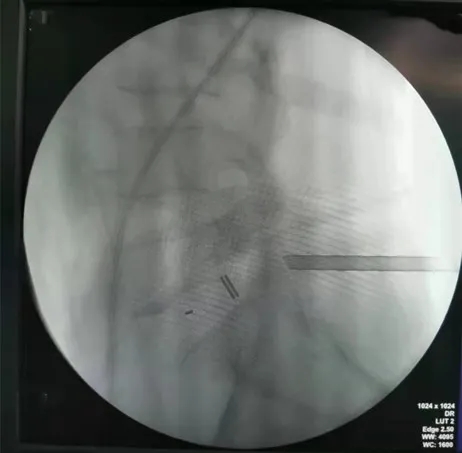

植入融合器的透視影像

C臂機(jī)監(jiān)視下經(jīng)皮微創(chuàng)置入椎弓根螺釘